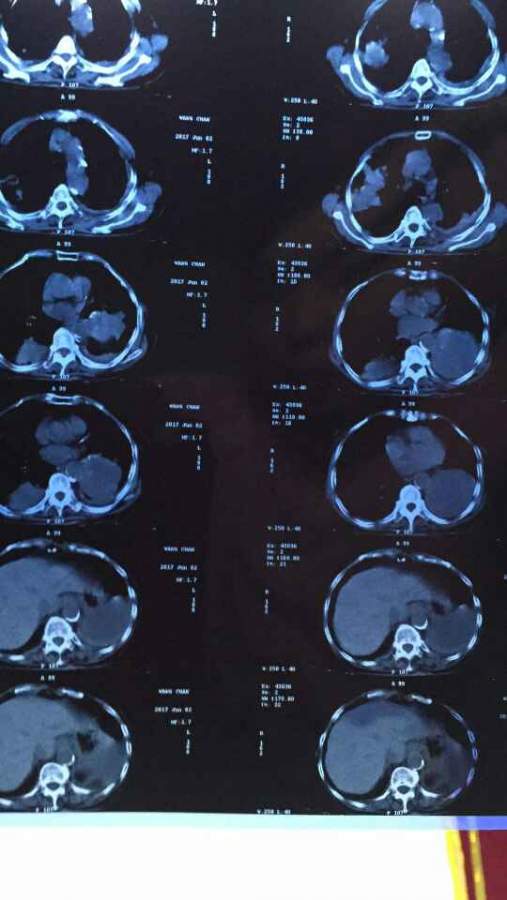

ÄÄλ´óÉñ£¬Äܹ»Ïêϸ½éÉÜϼ¸ÕÅctƬ×Ó ÒÑÓÐ3È˲ÎÓë

¼ÒÀïÍâÆÅµÄƬ×Ó£¬ÊǷΰ©£¬Ï£Íû¿ÉÒÔ´óÉñÏêϸ½éÉÜϲ¡±äÇé¿ö ·¢×ÔСľ³æAndroid¿Í»§¶Ë |

ÎÒ²»ÊÇÒ½Éú£¬Ö»ÄÜ˵·Î²¿µÄ°©±ä²¿·Ö»¹ÊÇ¿´×źÜÃ÷ÏԵ쬵ÚÒ»ÕÅÆ¬×ÓÖÐϱßÄǼ¸²ã£¬·Î²¿Öмä¸ßÁÁµÄ²¿·Ö¡£Ç°¼¸Ìì¸Õ¿´¹ý¼ÒÈËÀàËÆµÄƬ×Ó![]() ·¢×ÔСľ³æAndroid¿Í»§¶Ë |

Õâ¸öÖ»ÊÇÆÕͨCTƽɨ£¬¿´×ÅÏñ×ó·ÎÏÂÒ¶Ö×Áö£¬Ë«·Î¶à·¢×ªÒÆ£¬¸Î¼Ì·¢¶ñÐÔÖ×Áö´ý³ýÍâ¡£²»ÖªµÀÓÐûÓÐÈ¥Ò½Ôº¾ßÌåϵͳÖÎÁÆ ·¢×ÔСľ³æAndroid¿Í»§¶Ë |